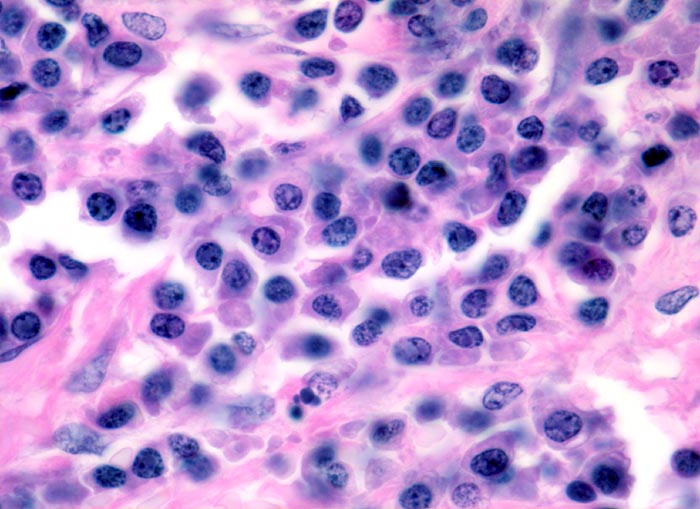

• In dieser Giemsa-Färbung sind die Plasmazellen gut erkennbar. Die Plasmazellen sind polymorph, vereinzelt mehrkernig. Exzentrisch im Zytoplasma lokalisierte vergrösserte Radspeichenkerne . Reichlich violettes Zytoplasma mit paranukleärer Aufhellung. Zellkerne teils mit vergrössertem Nukleolus.